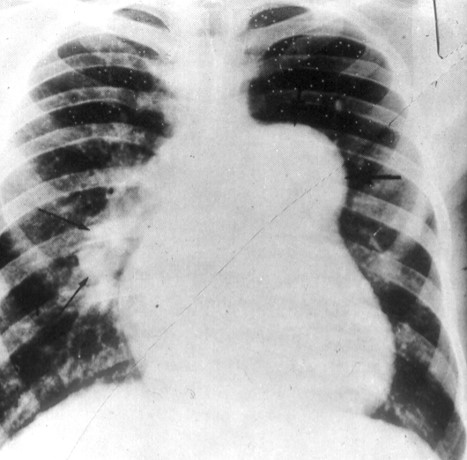

Panel B.

The patient's EKG shows signs of right atrial enlargement (P wave ≥ 2.5 mm tall in one or more inferior leads (II, III, AVF), >1.5 mm V1 with normal duration) and right ventricular hypertrophy (RV1 > 6mm, R:S ration V1 >1.0, RV1+SV6 ≥ 10.5 mm). His chest x-ray shows signs of chronic pulmonary hypertension (markedly enlarged main pulmonary artery segment, prominant right atrium and right pulmonary artery, and a rounded left heart border suggestive of RVH). This was due to pulmonary embolization of S. mansoni eggs.